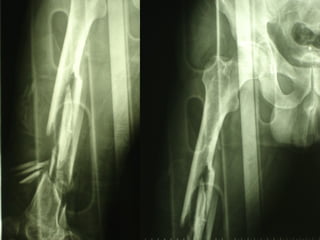

La lesione dell’apparato muscolo scheletrico che richiede  in ogni caso  un trattamento chirurgico con  priorità   assoluta  è la rottura dell’anello pelvico , che comporta una emorragia severa nel retro peritoneo e nella cavità peritoneale.

Immediata riduzione e fissazione del bacino

Se la risposta emodinamica a questo trattamento è buona il paziente verrà monitorato e potrà essere programmato un successivo intervento di osteosintesi definitiva

Angiografia e/o packing pelvico Se il paziente rimane instabile

Un’altra situazione di emergenza ortopedica è rappresentata dalle fratture delle ossa lunghe in pazienti con gravi traumi cranici e toracici